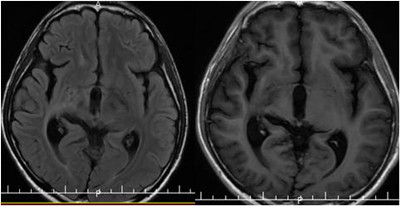

放疗结束后,小磊复查头颅MR,显示:原颅内多发病灶大部分明显缩小,部分消失。放疗后,继续予以六程辅助化疗,过程顺利。

现放疗后3年,小磊已正常学习生活,现就读高三,准备明年参加高考。

2017年10月 放疗后3年